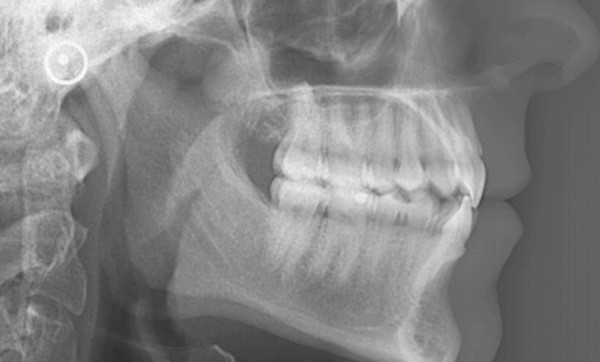

L’examen de la téléradiographie de profil fait apparaître un schéma squelettique normodivergent de classe I (fig. 8).